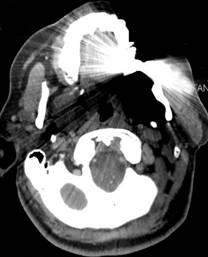

CT SCAN MRI

CT Scan and MR Scan from the same patient on the same day. On the left, metal scatter artifact from metallic fillings in the teeth almost completely obscure a tumor that is easily seen by MRI using metal suppressing techniques on the right.